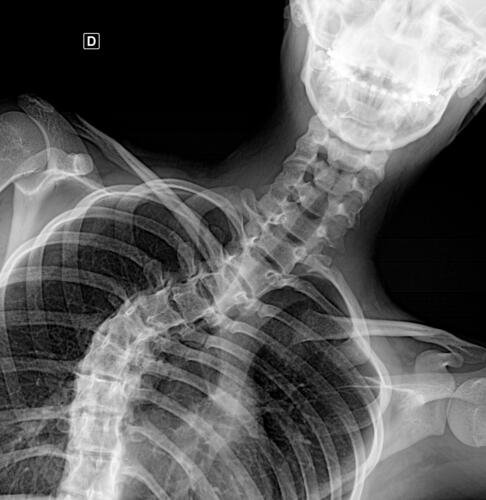

A Vá tem 13 anos e precisa urgentemente realizar uma cirurgia na coluna.Valentina foi surpreendida com o diagnóstico de escoliose hepática grave com 67 graus de desvio (desvio longitudinal da coluna), e precisa realizar com urgência a cirurgia corretiva, os exames foram realizados em Porto Alegre, mas a cirurgia está marcada para dia 13/07 em São Paulo devido a gravidade do caso, para isso a família terá que ficar residindo próximo ao hospital em São Paulo por no mínimo 30 dias para uma plena recuperação. Sabemos bem que qualquer procedimento cirúrgico é delicado, na coluna então nem se fala.Após o diagnóstico e o prognostico dessa doença a família se desfez de alguns bens (carro e moto) para cumprir os prazos dos exames e consultas, necessitando agora arrecadar o valor para a estadia da pequena Valentina e seu pós operatório (medicação, consultas e fisioterapia).

Em anexo os exames (laudo e imagens) para expressas a gravidade do caso.